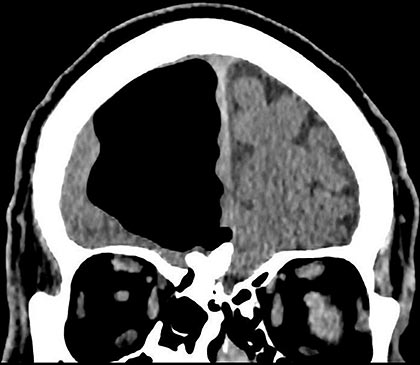

And speaking of airheads, doctors in occupied Ireland came across a rare, literal case of the phenomenon. A variety of physicians couldn’t figure out what was ailing an eighty-four-year-old man until they examined scans of his brain and found some of it wasn’t there. Instead, they discovered a large air pocket in his right frontal lobe where his brain used to be.